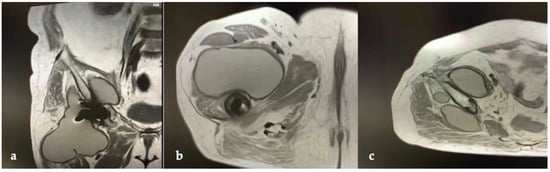

2. Case Report